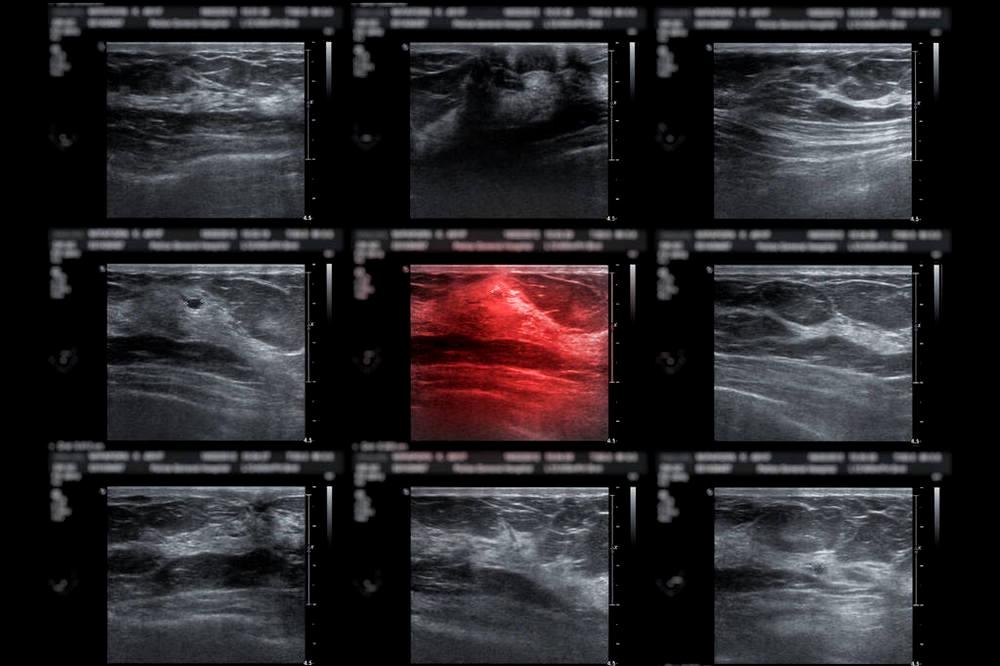

于是,我和老盧開始了“讓更多腦瘤患者用上立體定向放療”的新征程。我們創(chuàng)立了一家針對癌癥放療和人工智能技術(shù)產(chǎn)品研發(fā)的公司。2019年,我們與美國西南醫(yī)學中心和斯坦福大學展開了合作。目前,我們的平臺主要有3種AI模型:

自動勾畫/標記腦轉(zhuǎn)移瘤病灶的模型

基于SVM-放射組學的快速減少假陽性的模型

基于優(yōu)化輻射劑量圖并快速分割多個病灶到不同治療療程的模型

3個模型相輔相成,可快速標注病灶,最優(yōu)分配每次照射的輻射劑量。最讓我欣慰的是,患者延續(xù)生命的同時,生活質(zhì)量也更明顯地提高。我們在得克薩斯大學西南醫(yī)學中心等機構(gòu)為約100位進行了臨床治療。其中一位試驗患者腦瘤數(shù)超過100個。此外,我們的平臺可以延伸在頭頸、肺部、心臟等部位的應(yīng)用。

姜浩他們開發(fā)的腦癌立體定向放療項目的模型